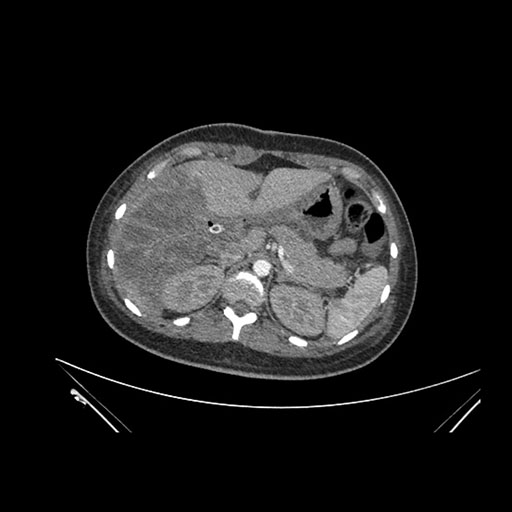

Axial Arterial

Imaging analysis

Based on initial findings, which issue(s) would you be most concerned about?